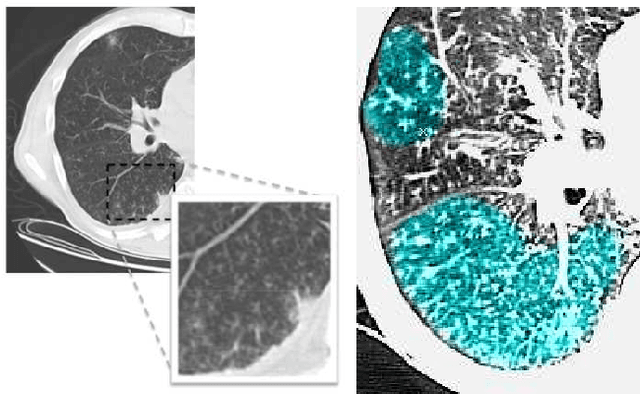

Abstract:Accurately predicting and detecting interstitial lung disease (ILD) patterns given any computed tomography (CT) slice without any pre-processing prerequisites, such as manually delineated regions of interest (ROIs), is a clinically desirable, yet challenging goal. The majority of existing work relies on manually-provided ILD ROIs to extract sampled 2D image patches from CT slices and, from there, performs patch-based ILD categorization. Acquiring manual ROIs is labor intensive and serves as a bottleneck towards fully-automated CT imaging ILD screening over large-scale populations. Furthermore, despite the considerable high frequency of more than one ILD pattern on a single CT slice, previous works are only designed to detect one ILD pattern per slice or patch. To tackle these two critical challenges, we present multi-label deep convolutional neural networks (CNNs) for detecting ILDs from holistic CT slices (instead of ROIs or sub-images). Conventional single-labeled CNN models can be augmented to cope with the possible presence of multiple ILD pattern labels, via 1) continuous-valued deep regression based robust norm loss functions or 2) a categorical objective as the sum of element-wise binary logistic losses. Our methods are evaluated and validated using a publicly available database of 658 patient CT scans under five-fold cross-validation, achieving promising performance on detecting four major ILD patterns: Ground Glass, Reticular, Honeycomb, and Emphysema. We also investigate the effectiveness of a CNN activation-based deep-feature encoding scheme using Fisher vector encoding, which treats ILD detection as spatially-unordered deep texture classification.